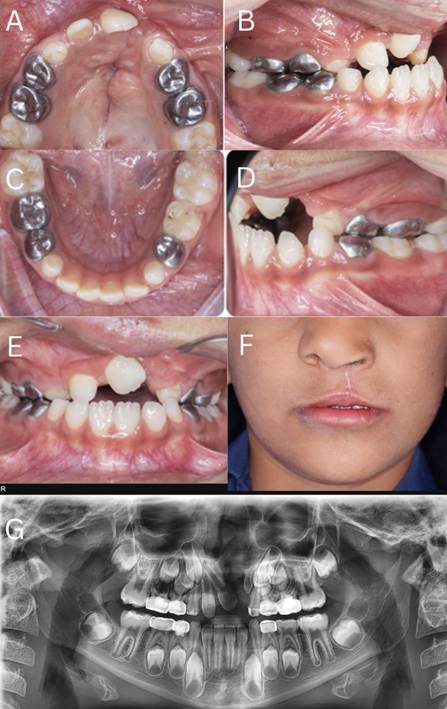

Facial esthetics improved, with better lip support compared to the preoperative state. Radiographic evaluation suggested that orthodontic adjustments were necessary for the upper right central and lateral incisors to guide the proper eruption of the permanent canines. Following completion of maxillary growth, implant restoration was planned for the missing upper left central incisor to restore optimal function and appearance (Figure 7).

Figure 7. A) Upper-Arch Occlusal View Showing the Residual Cleft of the Maxilla, B) Right Lateral Occlusal/Bite View After Maxillary Expansion

Tooth 53 remained in crossbite, and tooth 52 was in an edge-to-edge (tip-to-tip) relationship.

C) Mandibular Occlusal View Demonstrating a Well-Formed Arch with Very Mild Anterior Crowding, D) Left Lateral Bite View Showing Persistent Crossbite of Tooth 63, E) Anterior Intraoral View Showing Residual Crossbite Primarily Attributable to Unerupted Permanent Teeth, F) Frontal Facial View Showing Improved Lip Support and Facial Esthetics Following Treatment, G) Postoperative Panoramic Radiograph

The upper right central and lateral incisors required orthodontic repositioning to guide the eruption of the permanent canines; the congenitally missing upper left central incisor was restored with an implant after maxillary growth was completed.